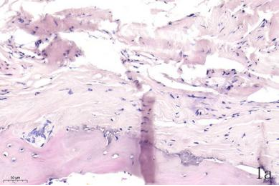

NDN(Necdin)属于黑色素瘤抗原(MAGE)家族,由60多个基因构成共享高度保守的MAGE同源结构域(MHD)[6,7]。最近几年的研究提出NDN是一种新的抑癌基因,其在卵巢癌[8]、乳腺癌[9]和黑色素瘤[10]等的组织和细胞系中低表达,过表达NDN可以抑制其生长,但NDN在骨肉瘤中的作用及机制尚不清楚。为探讨NDN在骨肉瘤中的作用及途径,我们收集了骨肉瘤患者的石蜡标本以及临床信息,对其进行了免疫组化检测及生存分析。通过对骨组织和骨肉瘤HE染色发现,骨组织组,骨密质呈板层状,陷窝中可见骨细胞呈梭形排列( 图1 a 1b) ;骨肉瘤组,瘤细胞呈多角形,核大深染,核分裂多见,瘤细胞呈车辐状排列,瘤细胞间可见少量肿瘤性骨质形成(图1c1d)。同时通过免疫组化发现,NDN表达主要位于细胞的胞核中。NDN在骨肉瘤组织中的表达率为29.4%(15/51)(图1c1d),明显低于瘤旁骨组织阳性表达率80%(8/10)(图1a1b)。